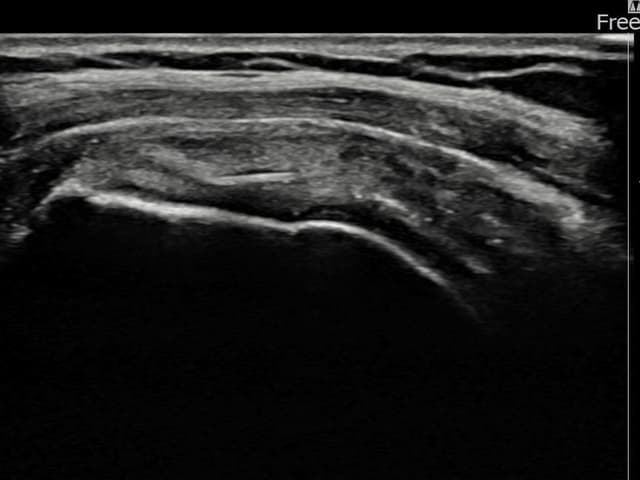

[経過期間: 23.07.18~23.09.14]

[縫縮術] 超音波検査にて左 棘上筋腱 광범위 部分断裂(15mm × 6mm (腱厚の約70%欠損))を確認。縫縮術施行後、腱の連続性が回復し、日常生活に復帰されました。